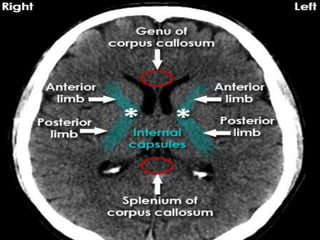

Anatomical Land marks.

• Cortex and division into various lobes.

• Subcortical structures including basal

ganglia,thalamus .